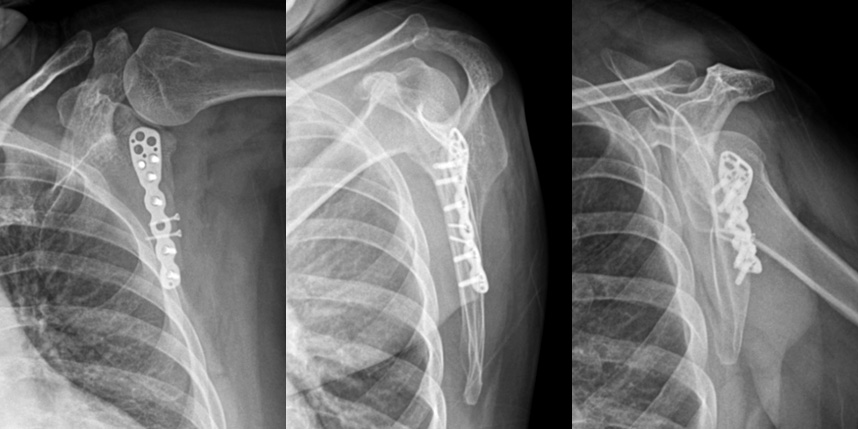

골절은 정확하게 골절편을 잘 맞추고 고정하는 것이 중요합니다. 특히 관절면을 잘 맞추는 것이 중요합니다.

또한 수술 이후 빠른 재활을 통해 전체적인 회복을 도모하여 일상으로 빨리 복귀할수 있도록 해야 합니다.

상완골 골절